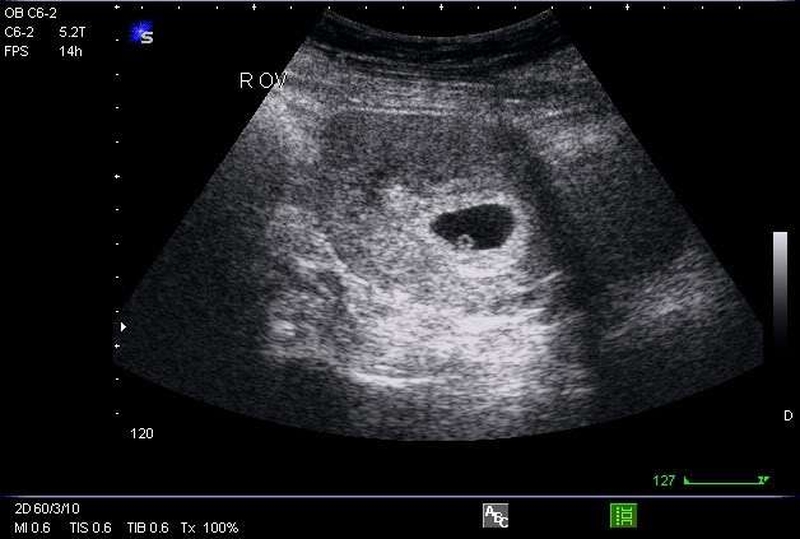

Trong thời kỳ mang thai thì tim thai sẽ hình thành và bắt đầu đập kể từ ngày thứ 22 sau khi thụ thai. Thông thường tim thai sẽ xuất hiện vào tuần thứ 6 đến 7 của thai kỳ thông qua các kỹ thuật siêu âm hiện đại, giúp mẹ có thể dễ dàng nhận biết và nghe được tim thai.

Khoảng thời gian thích hợp để siêu âm tim thai là tuần thứ 6 - 9 của thai kỳ, giai đoạn này sẽ giúp mẹ bầu xác định chính xác mình có mang thai hay không, nhận biết được tuổi thai và đồng thời kiểm tra tim thai có đang hoạt động hay không. Bên cạnh đó thông qua việc siêu âm tim thai sẽ có thể sàng lọc được tình trạng khuyết tật tim bẩm sinh, tim một thất, teo van động mạch phổi,.... Chính vì vậy mà không nên bỏ qua siêu âm tim thai ở giai đoạn này, bởi nếu không thăm khám, không biết được sự phát triển, tồn tại của bé sẽ rất dễ gặp phải những vấn đề không mong muốn.